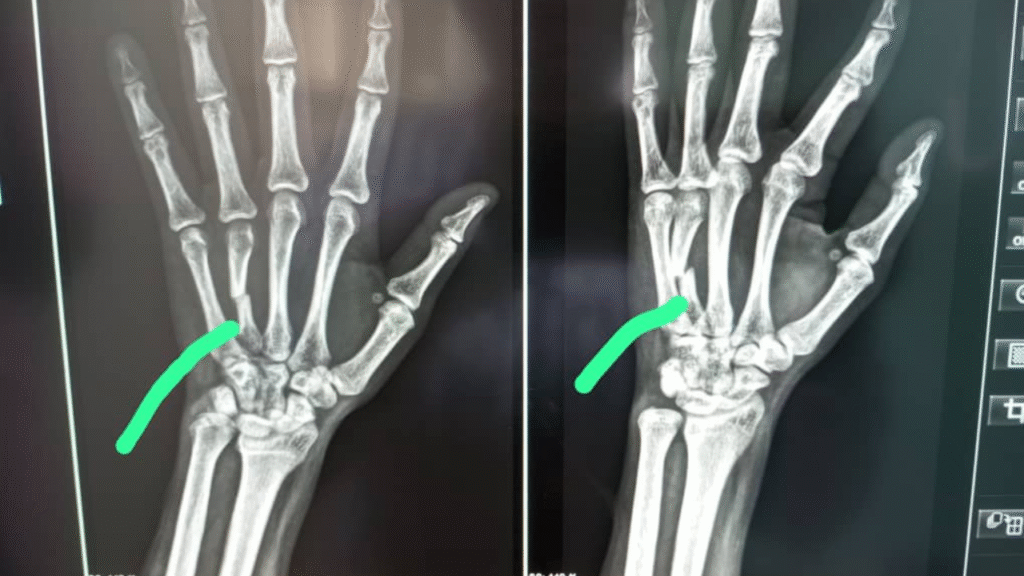

The photo showed a clear fracture, which required surgery with a metal plate.